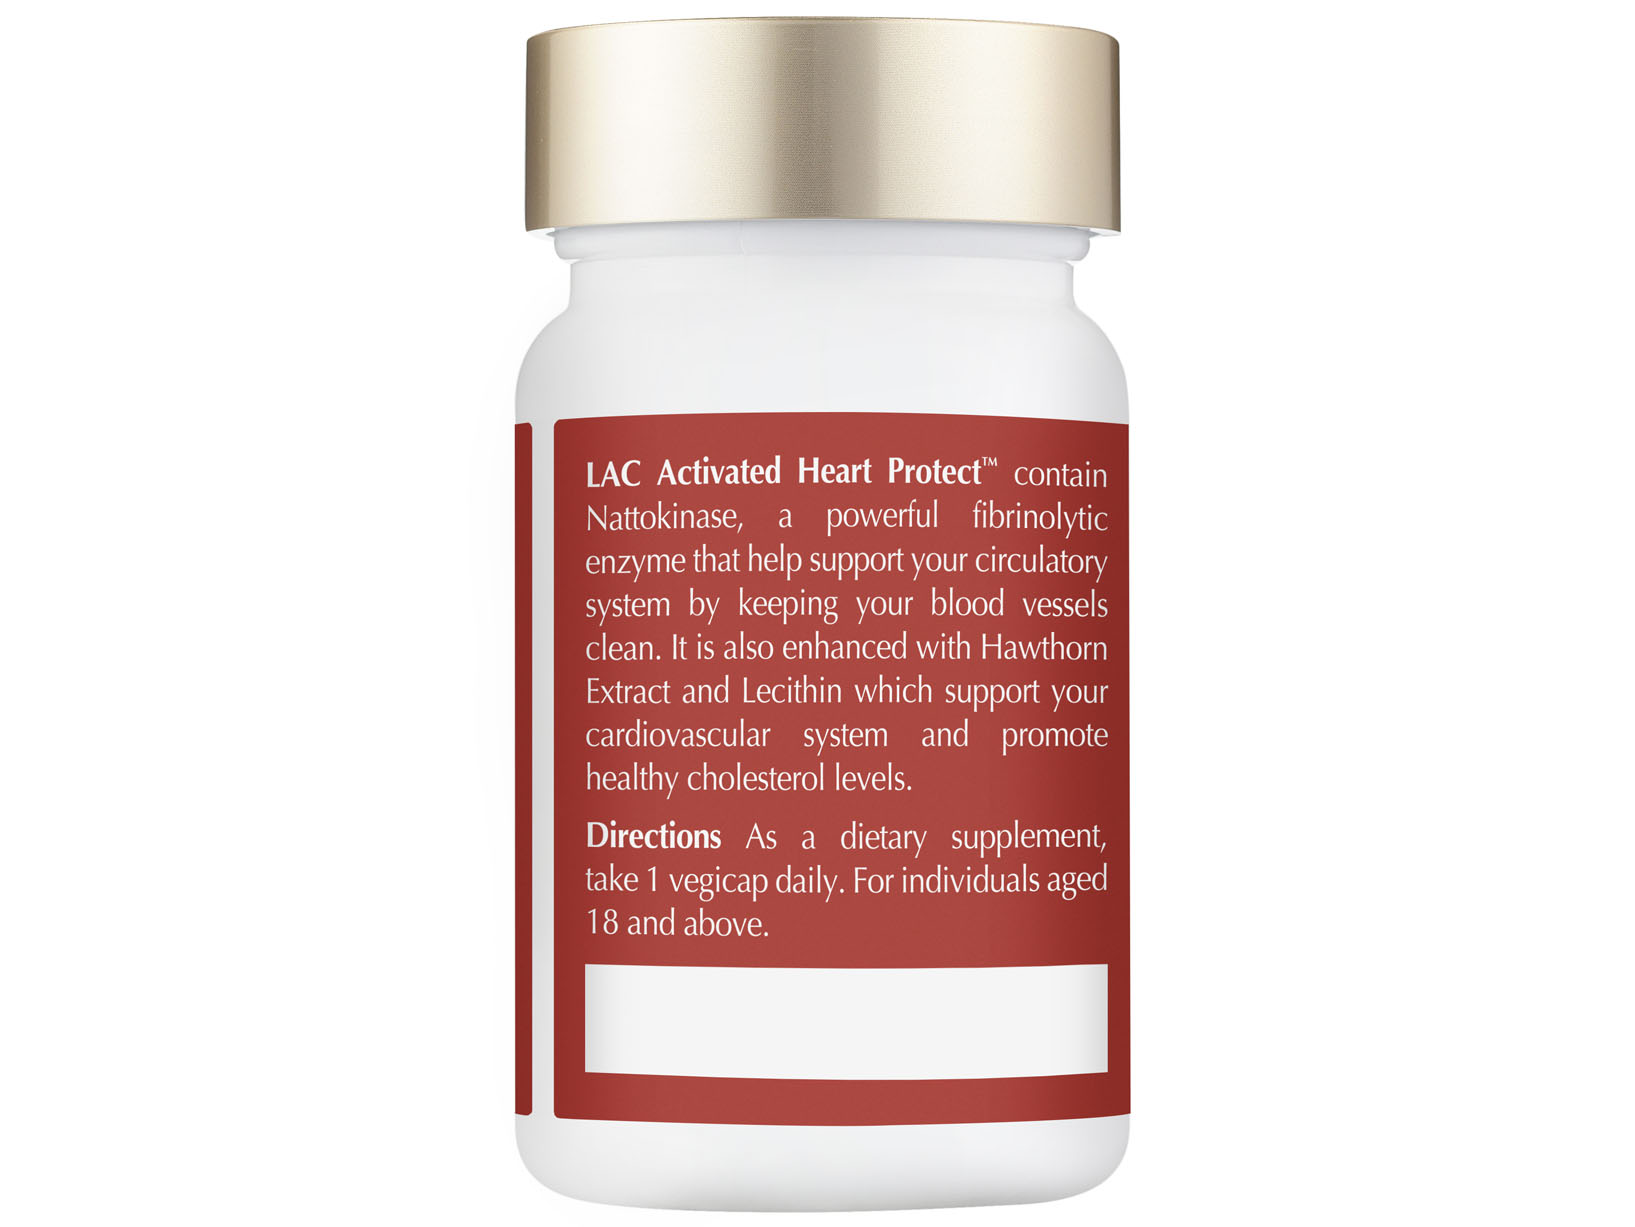

BOOST YOUR HEART HEALTH WITH

LAC ACTIVATED HEART PROTECT™